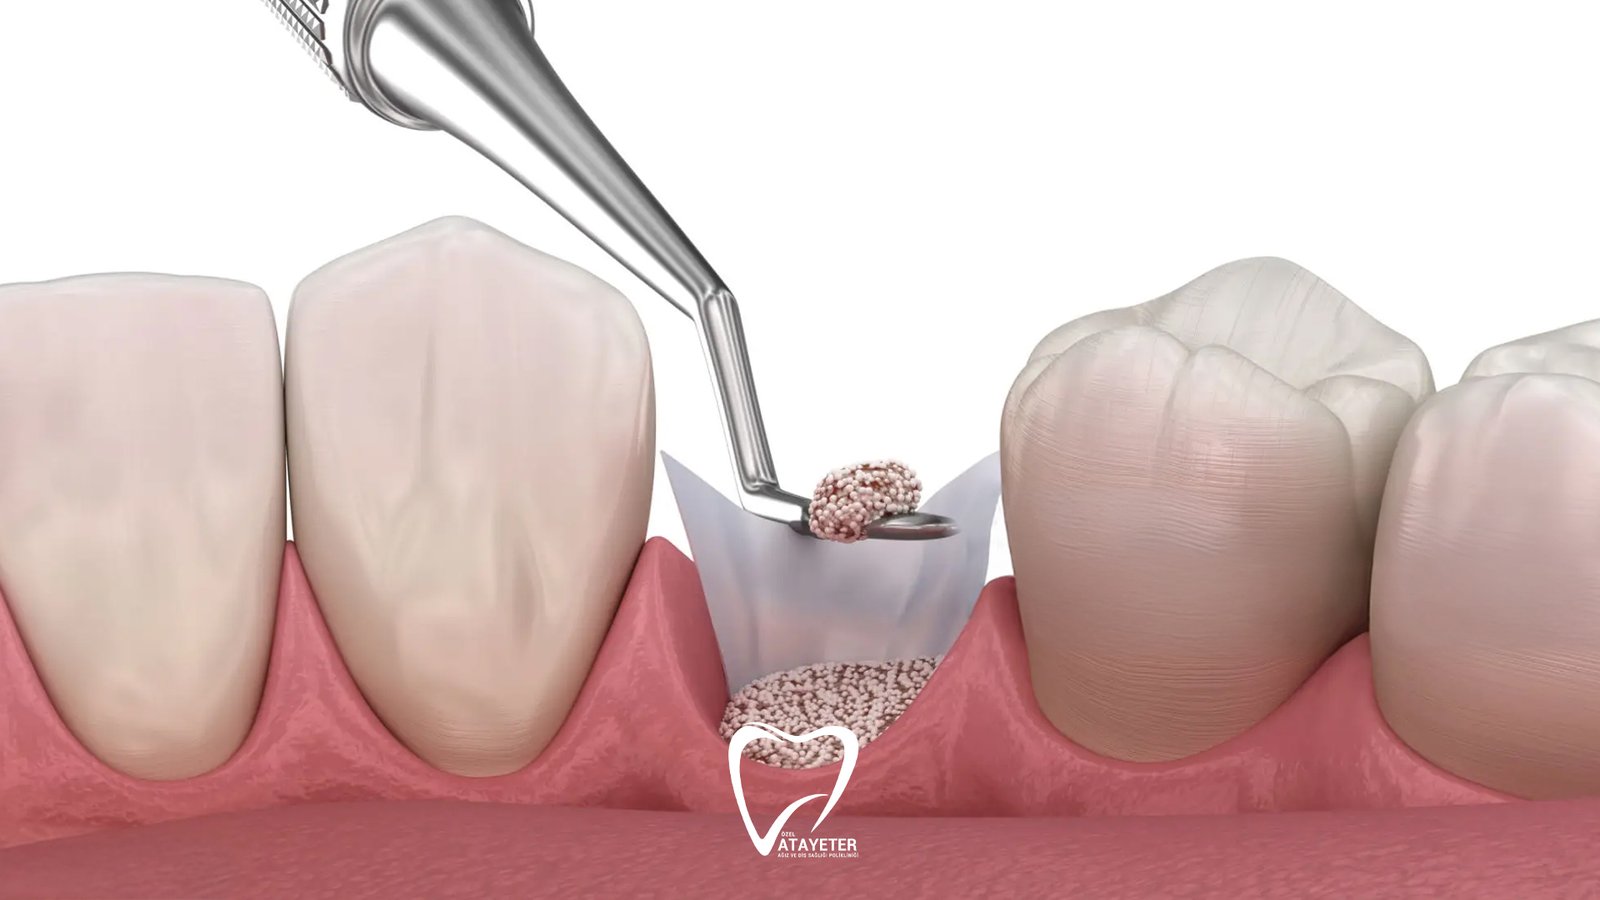

After the preparation is complete, a special bone graft material is placed into the area where bone loss exists. These materials can come from different sources. In some cases, the patient’s own bone may be used, while in other situations human derived, animal derived, or synthetic bone materials produced in laboratories may be preferred. Today, most graft materials used in dentistry are specially designed to be safe and fully compatible with the human body. Once placed, they act as a framework that supports the growth of new bone tissue.

The grafted area is often covered with a thin protective membrane after the material is placed. This membrane helps protect the graft and supports a healthier healing process. It also encourages the new bone tissue to develop in a more organized way. Finally, the area is closed with small stitches, and the healing process begins.